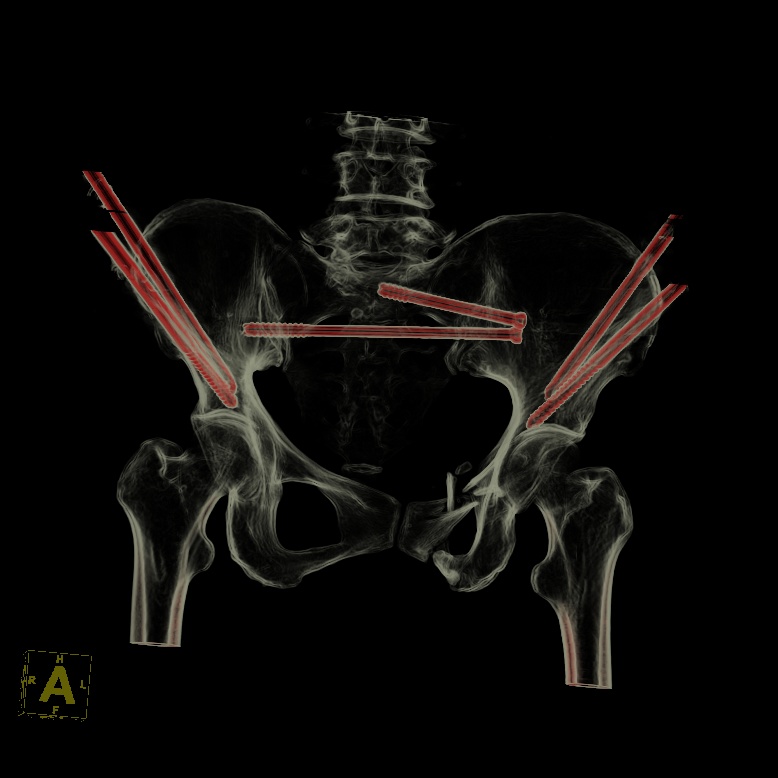

术后骨盆CT片

在手术过程中,骨科手术机器人展现了卓越的性能。通过精确的术前规划和实时的术中导航,医生仅通过几个微小的切口(每个仅1cm长),便成功地置入了2枚骶髂螺钉和4枚骨盆外固定Schanz钉。在骨科手术机器人的辅助下,此次手术时间较传统手术明显缩短,术中失血量仅约20ml,手术创伤小,大大降低了手术风险。值得注意的是,此次手术采用新型的骨盆支架外固定术,该技术可将Schanz钉完全置入髂骨内外板之间并打入髋臼顶相对致密且丰厚的骨质内,使骨盆骨折得到了有效固定,且该技术具有基于触诊、不依赖透视、置钉精准且深入的优势。得益于骨科手术机器人微创手术治疗,该患者在术后3天即顺利出院,体现了现代快速康复理念。骨科手术机器人技术的顺利开展,标志着金瓶梅电影 在数字智能治疗复杂骨盆骨折疾病方面迈入精准微创新高度。